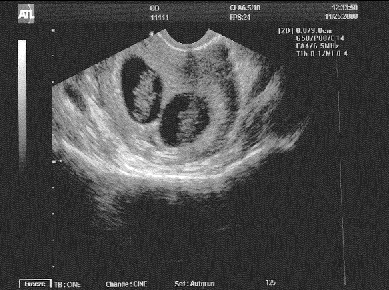

Tuesday, November 25 – Our first doctor appointment. He did an ultrasound and showed us the beating heart of our child. Amazing!!! Then he shifted the sensor and discovered the beating heart of our SECOND child. We’re having twins! I was speechless, dumbfounded, nearly incapacitated. Dan took it in stride. The doctor measured the babies (18 mm) to determine the date of conception and advised that our due date was July 5. He also told us to expect an early appearance since twins have a tendency to run out of room before their due date. When the physical exam was complete the doctor said, “We have a lot to talk about.” I responded, “Whatever you’re going to say, you should have told me before the ultrasound.” I was still pretty stunned and didn’t know how much of what he was going to say would really register. Afterwards, I went back to work. I might have just gone home and called it a day, but Dan was leaving from the doctor’s office to go to Shafter to pick up Grandma Siemens so she could spend Thanksgiving in Livermore with everyone. I composed myself as best I could and went back to work. I’m not sure how much work I actually accomplished (every other word that went through my head was “TWINS!”), but I made it through the rest of the day without anyone asking what was up. Not sure I could have maintained my silence in the face of a direct question.